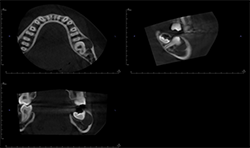

Case 2:66-year-old woman with edentulous maxillae

Two-dimensional imaging can’t evaluate the volume of the alveolar process accurately, especially in the buccolingual direction (Fig. 3)

CBCT imaging shows the volume of the alveolar process in any direction for implant treatment planning. (Figs. 4A, 4B) CBCT software allows one to measure the height and width of the alveolar ridge (Fig. 4C). This patient doesn’t have adequate bone volume for implant placement in the posterior left maxilla (Fig. 4D). Due to the severe alveolar ridge resorption, gaining adequate bone volume was recommended.